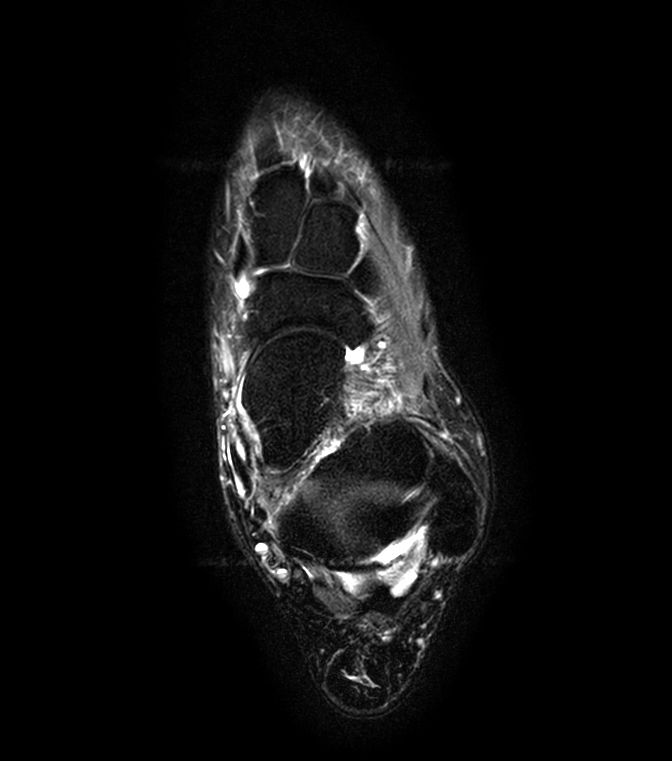

Imaging with the dS 16ch FootAnkle coil

General Hospital Sint Blasius, Dendermonde, Belgium

Patient who was referred for imaging of the achilles tendon